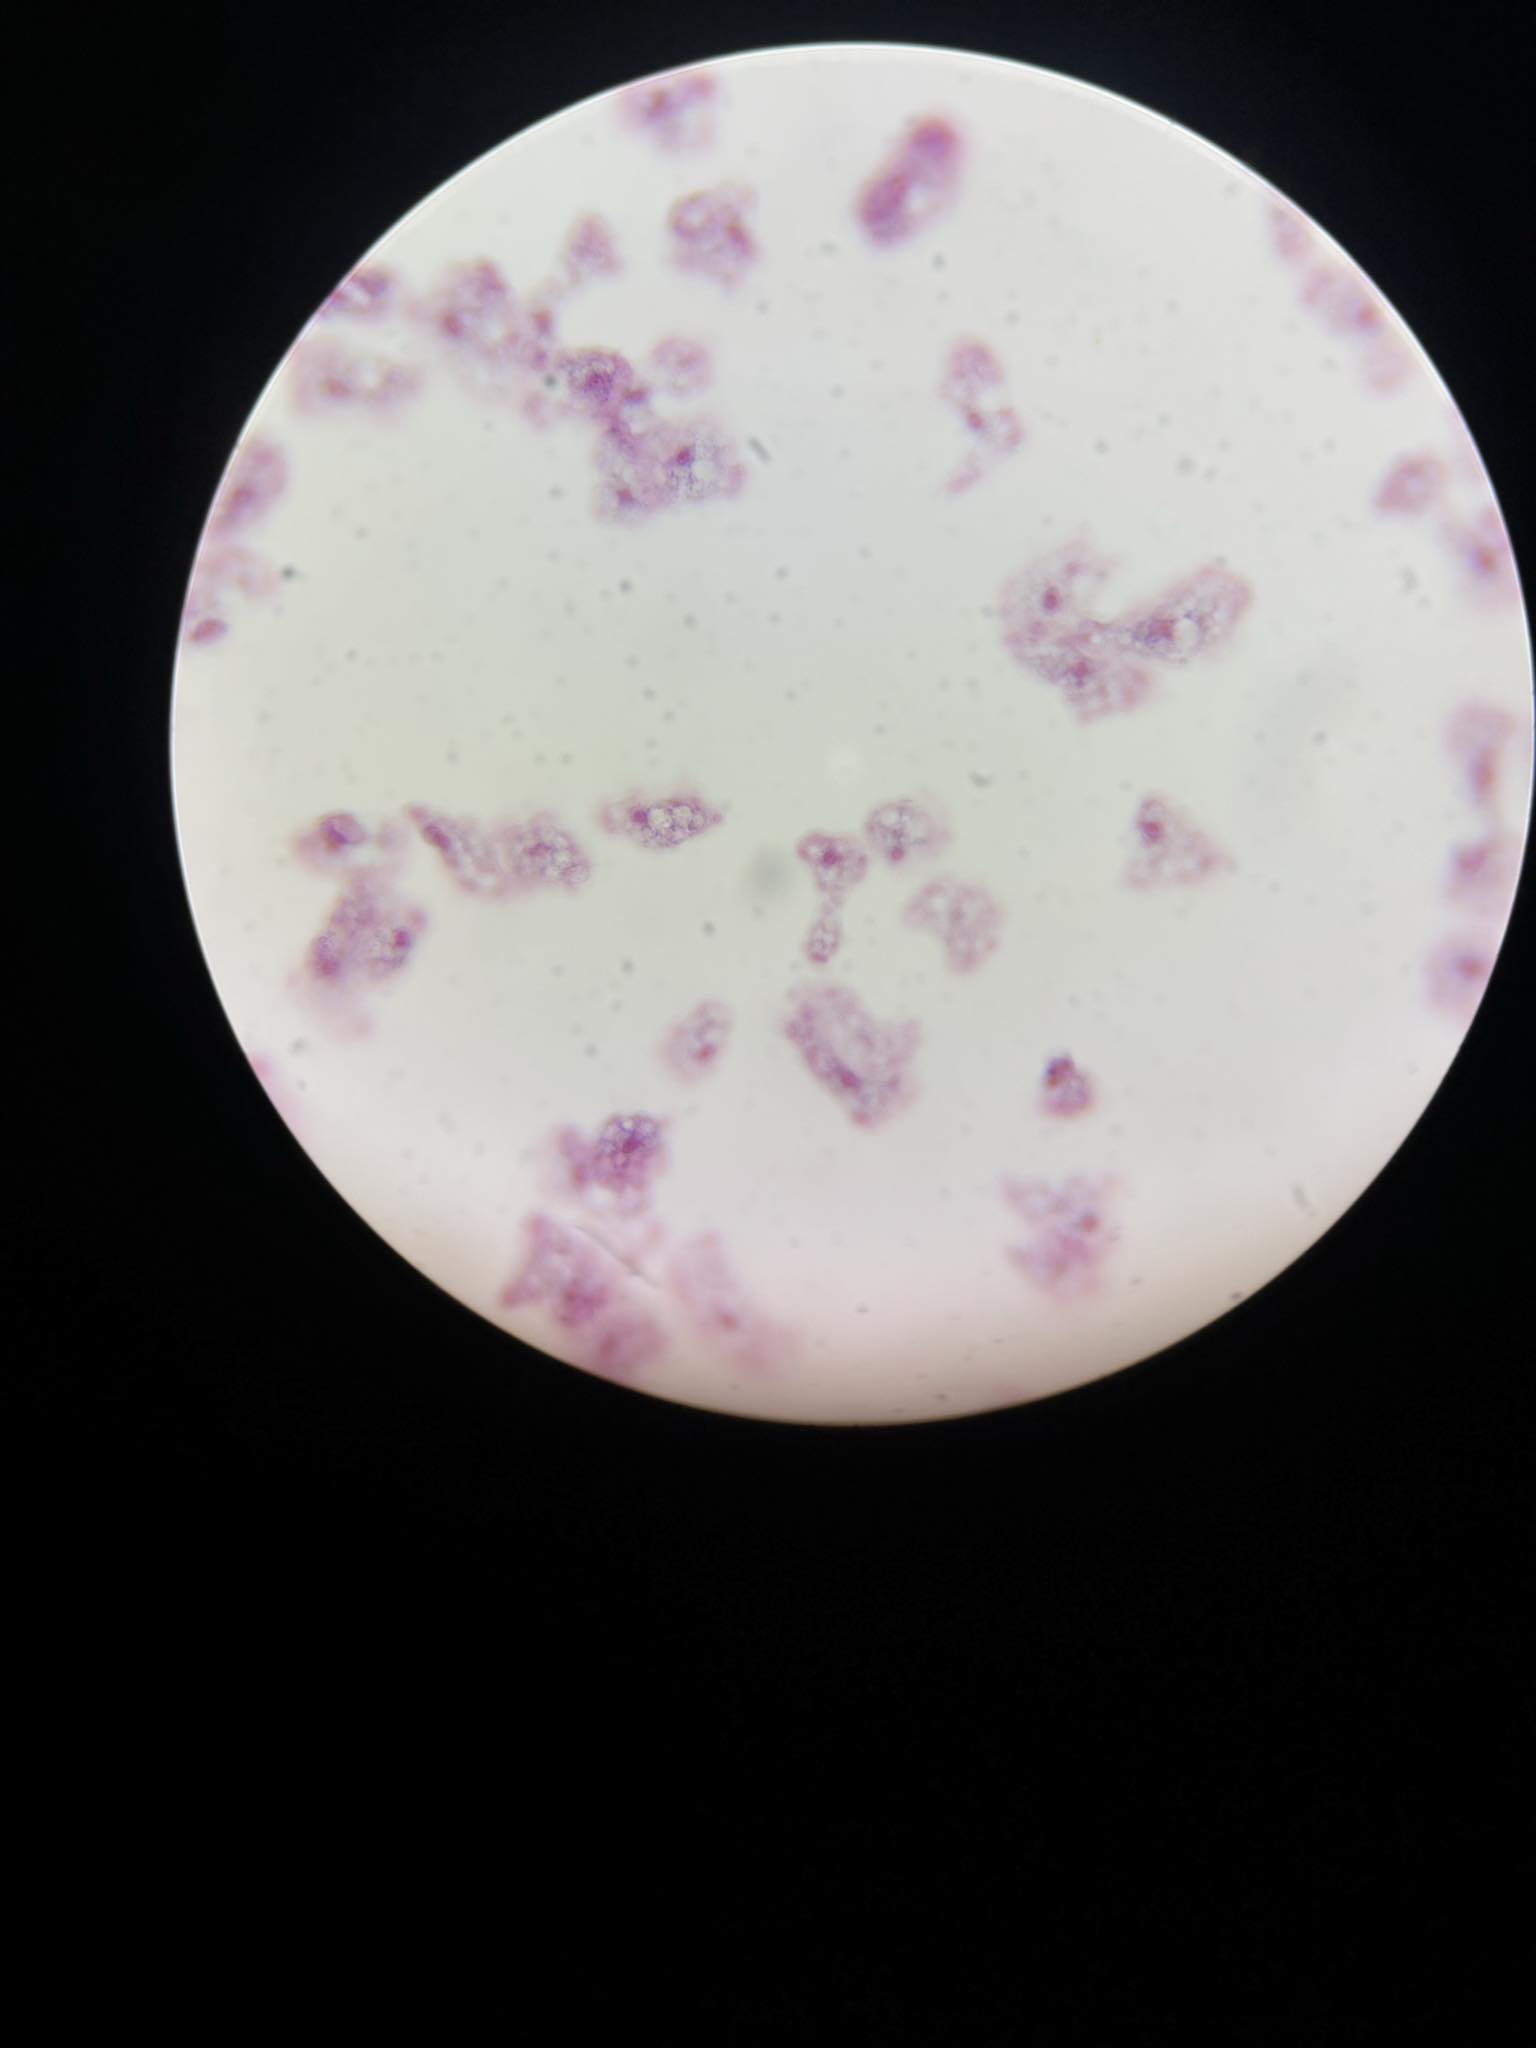

plasmodium falciparum stadia schizogonii krwinkowej

plasmodium falciparum stadia schizogonii krwinkowej